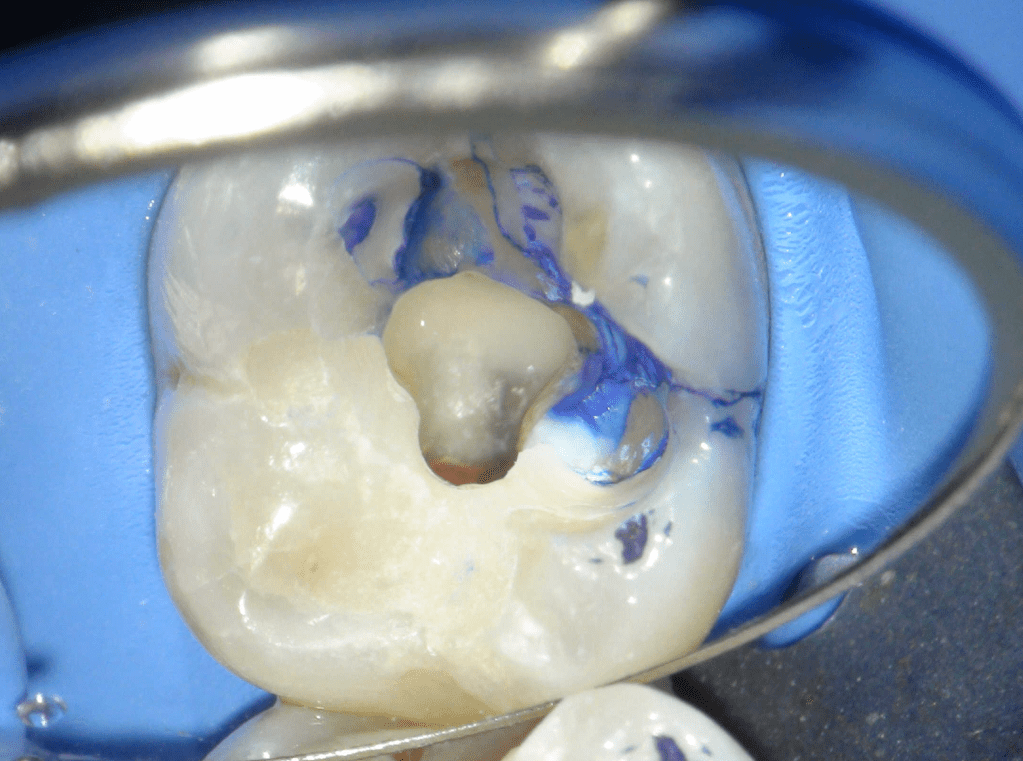

Pulpotomía biodentine + reco preendio